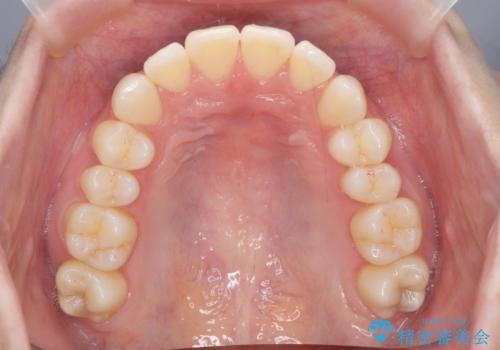

昔ワイヤー矯正をして後戻りした 軽度のがたつき モニター矯正

- 矯正治療後の後戻りを主訴に来院。

マウスピース矯正で再矯正を行いました。

再度の後戻りを防ぐため、下顎前歯の裏にはワイヤーを貼る保定を行っています。